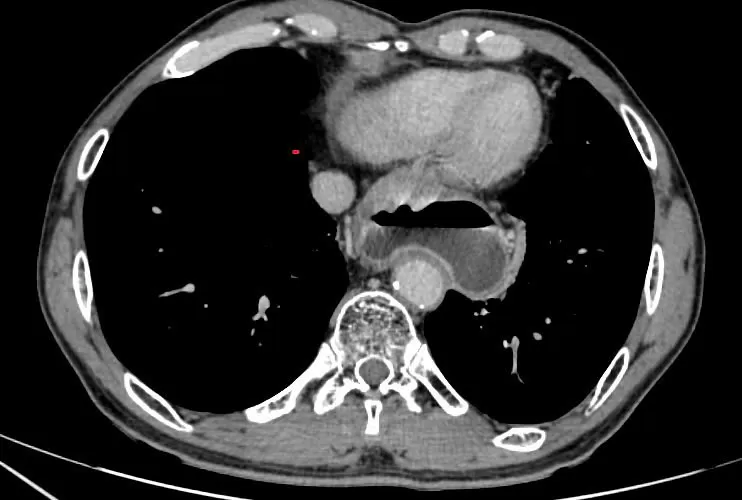

Hình ảnh tổn thương ống dạ dày trên chụp cắt lớp vi tính